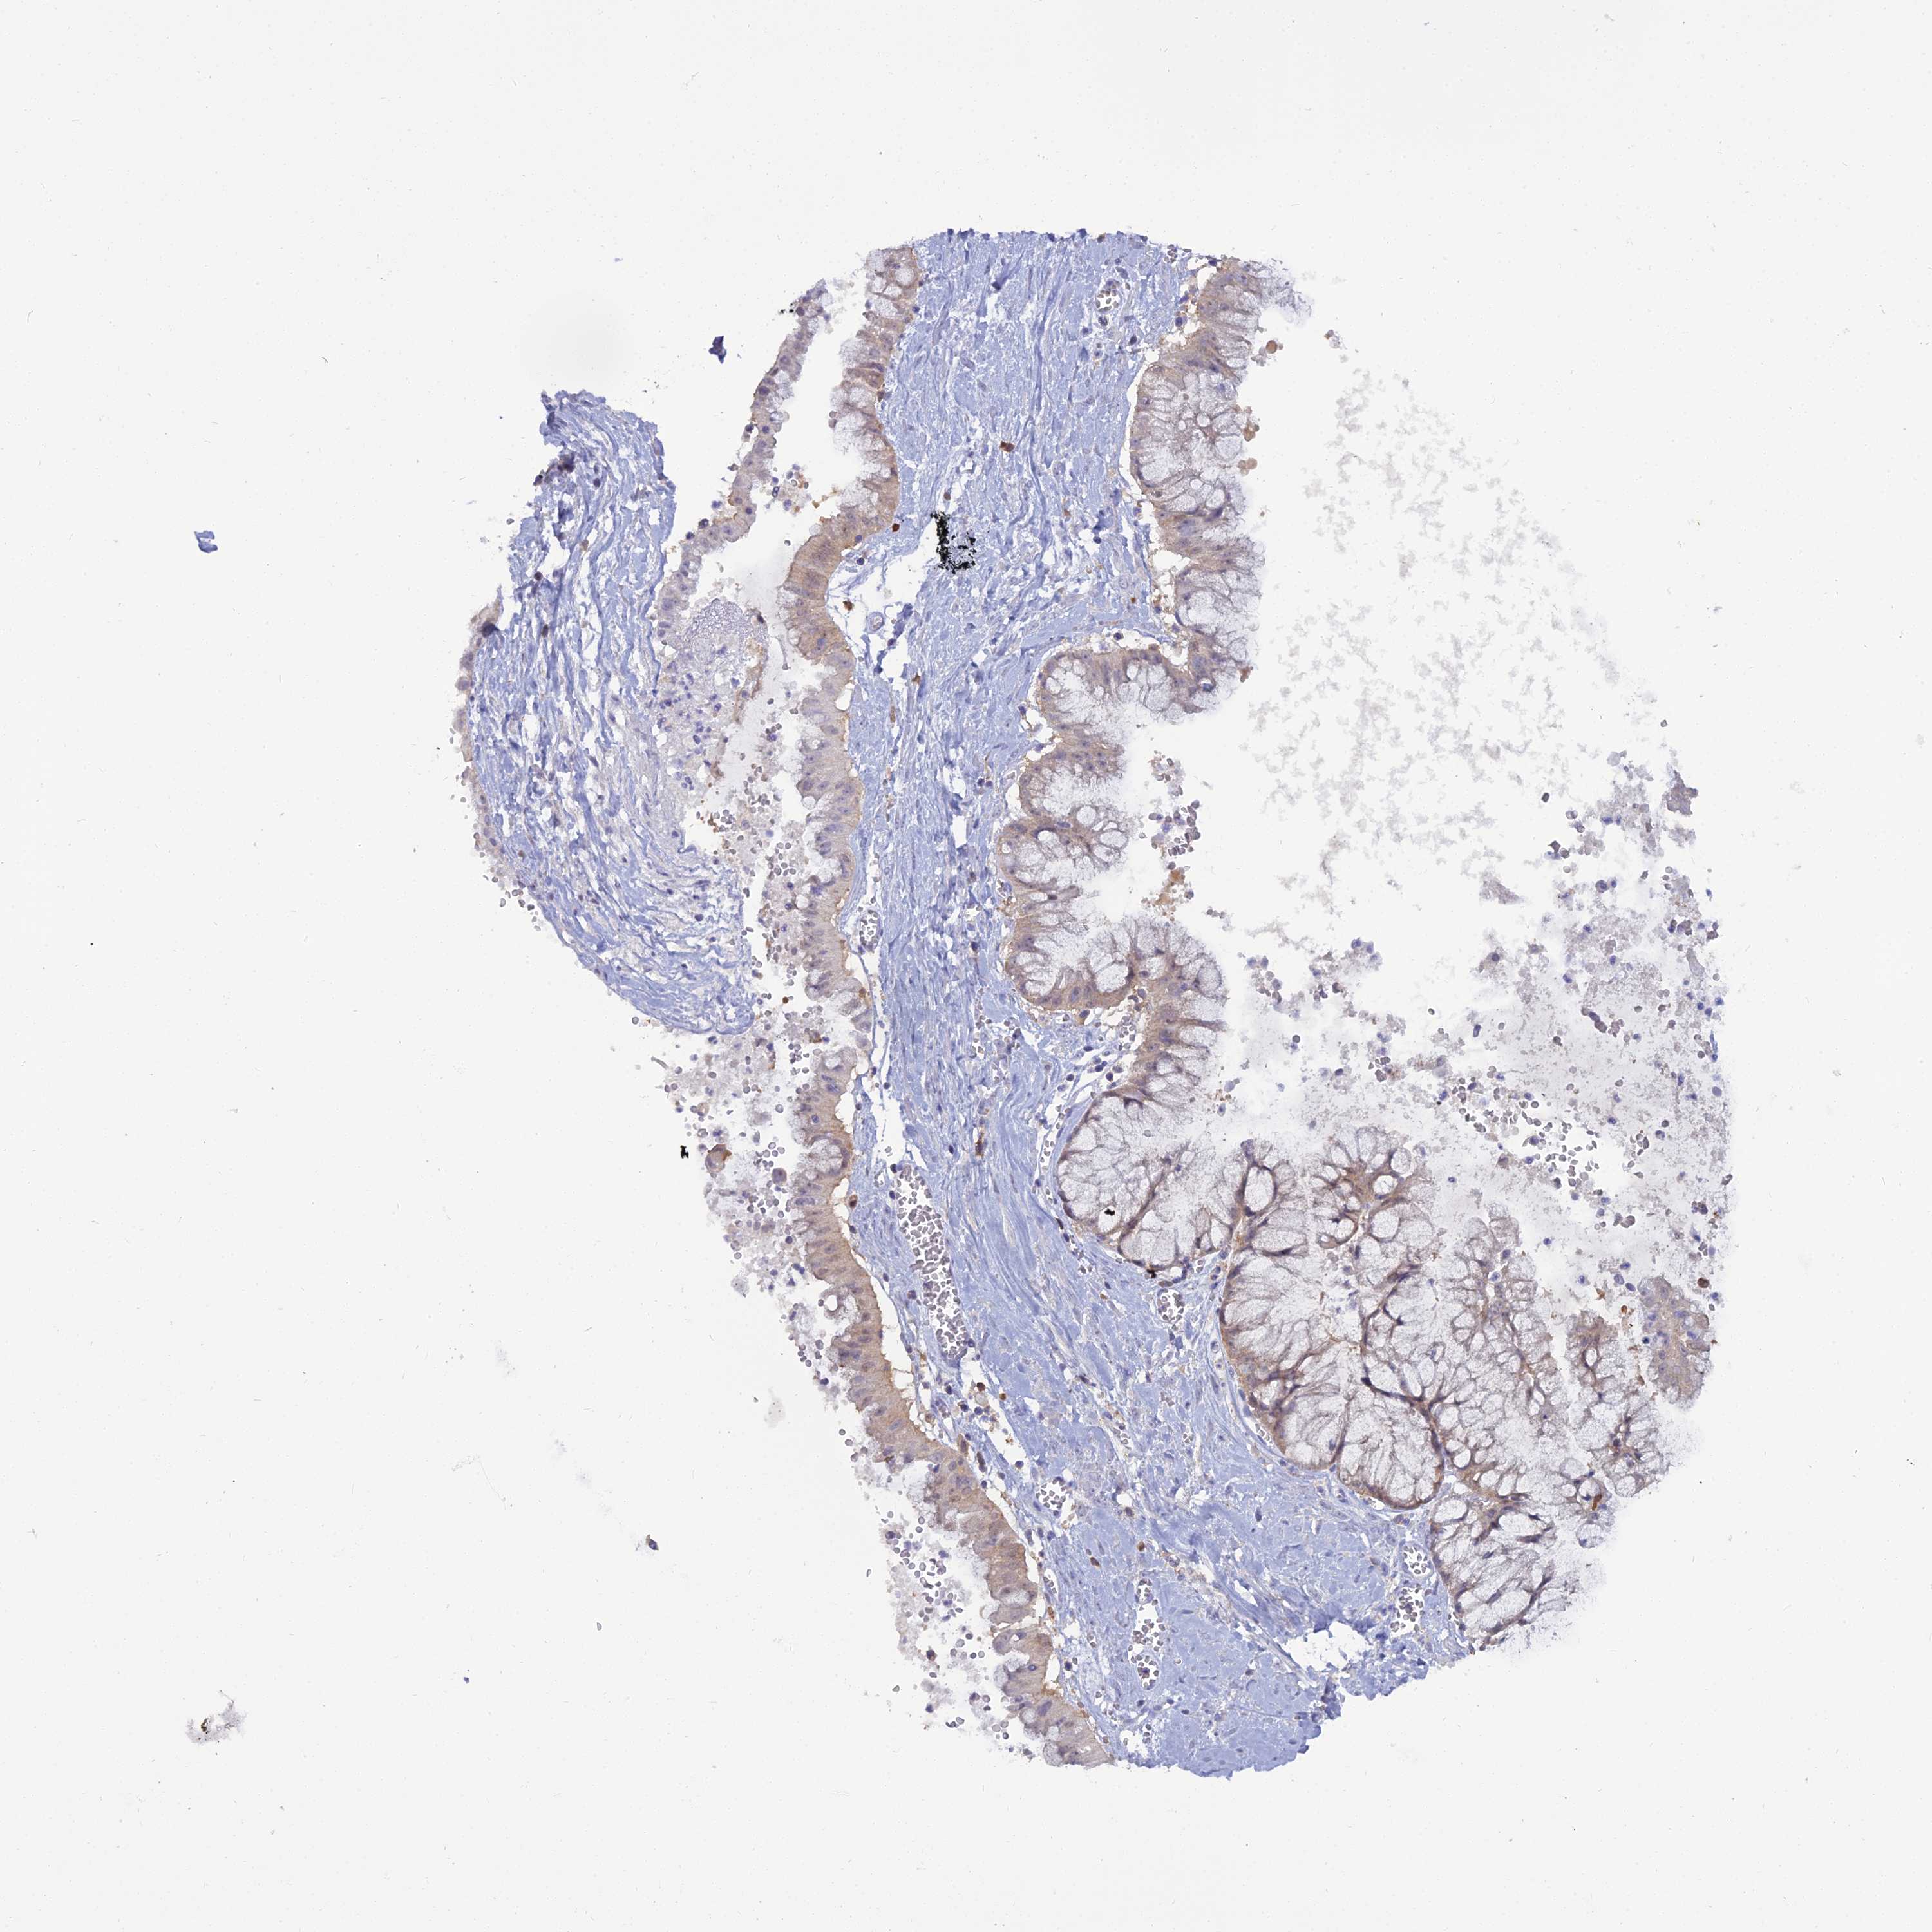

OVARIAN CANCER - Protein expressioni

A mouse-over function shows sample information and annotation data. Click on an image to view it in a full screen mode. Samples can be filtered based on level of antibody staining by selecting one or several of the following categories: high, medium, low and not detected. The assay and annotation is described here.

Note that samples used for immunohistochemistry by the Human Protein Atlas do not correspond to samples in the TCGA dataset.

Antibody stainingi

Antibody staining in the annotated cell types in the current human tissue is reported as not detected, low, medium, or high, based on conventional immunohistochemistry profiling in selected tissues. This score is based on the combination of the staining intensity and fraction of stained cells.

Each image is clickable and will lead to virtual microscopy that enables deeper exploration of all samples and also displays staining intensity scores, fraction scores and subcellular localization as well as patient and tissue information for each sample.

Antibody HPA038309

Antibody HPA038310

Antibody CAB009333

Antibody CAB016291

Cystadenocarcinoma, serous, NOS

Carcinoma, NOS

Cystadenocarcinoma, mucinous, NOS

Carcinoma, endometroid